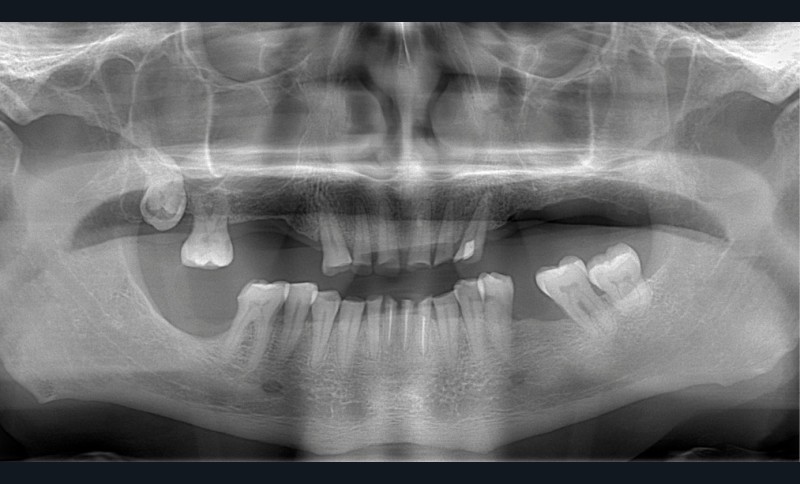

Un patient de 68 ans arrive au cabinet ; il présente de nombreux édentements ainsi qu’une usure parafonctionnelle très avancée.

Examen clinique (fig. 1-6)

• L’examen intrabuccal montre de nombreux édentements non compensés (14, 15, 16, 24, 25, 26, 27, 47 et 36) ainsi que des pertes de substance très importantes, notamment dans le secteur antérieur.

Une attrition sévère, couplée à une occlusion sans calage postérieur, a engendré des difficultés pour s’alimenter.

– égressions compensatoires.